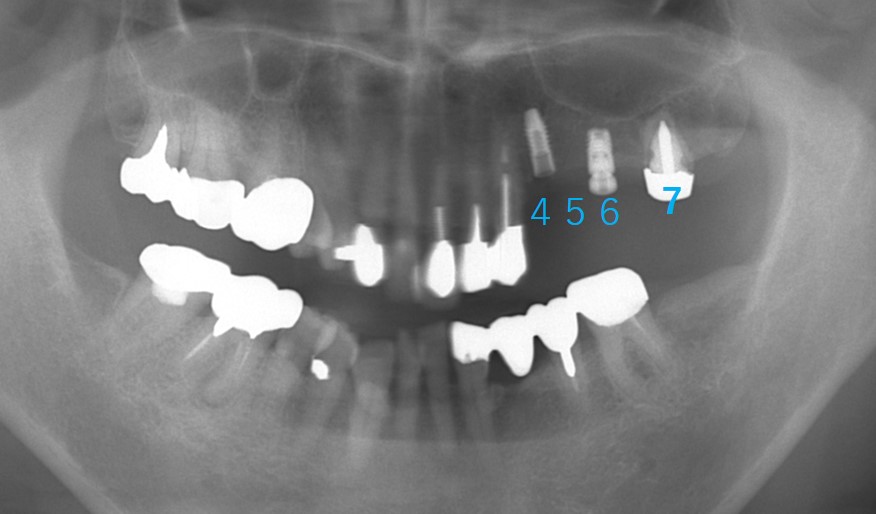

それ後8年経過、現在78歳になられました。

7番は内冠(被せものを2重にして取り外せる)を装着して、インプラントと連結したブリッジになっています。